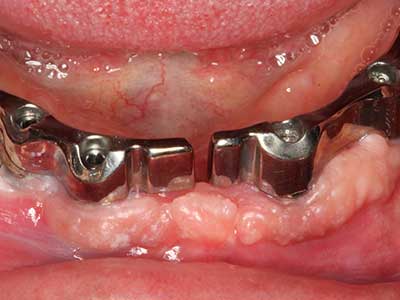

Como ya se ha demostrado en el pasado, básicamente cualquier procedimiento de cirugía de hueso representa una posible indicación para la cirugía piezoeléctrica. Así, la preparación del segmento móvil en la osteogénesis de distracción (fig. 23-25) y en la osteotomía de sándwich puede realizarse con piezas especiales, sin poner en peligro el suministro sanguíneo de la parte crestal, que resulta esencial para el éxito de ambas técnicas (González-García, Diniz-Freitas et al. 2008).

Para la extracción de implantes es posible realizar la preparación de una tapa ósea vestibular que, tras retirar el tornillo del implante, vuelve a fijarse y, de este modo, mantiene el contorno de la apófisis alveolar.

En la cirugía del seno maxilar surgen otros campos de aplicación: En este punto, tras la preparación concéntrica de una tapa ósea de la pared del seno maxilar (que suele tener forma trapezoidal), es posible eliminar patologías y cuerpos extraños del seno maxilar. La tapa ósea se repone después de finalizar la parte intra-antral de la operación y se asegura frente a una posible dislocación mediante cuñas o suturas adaptables.